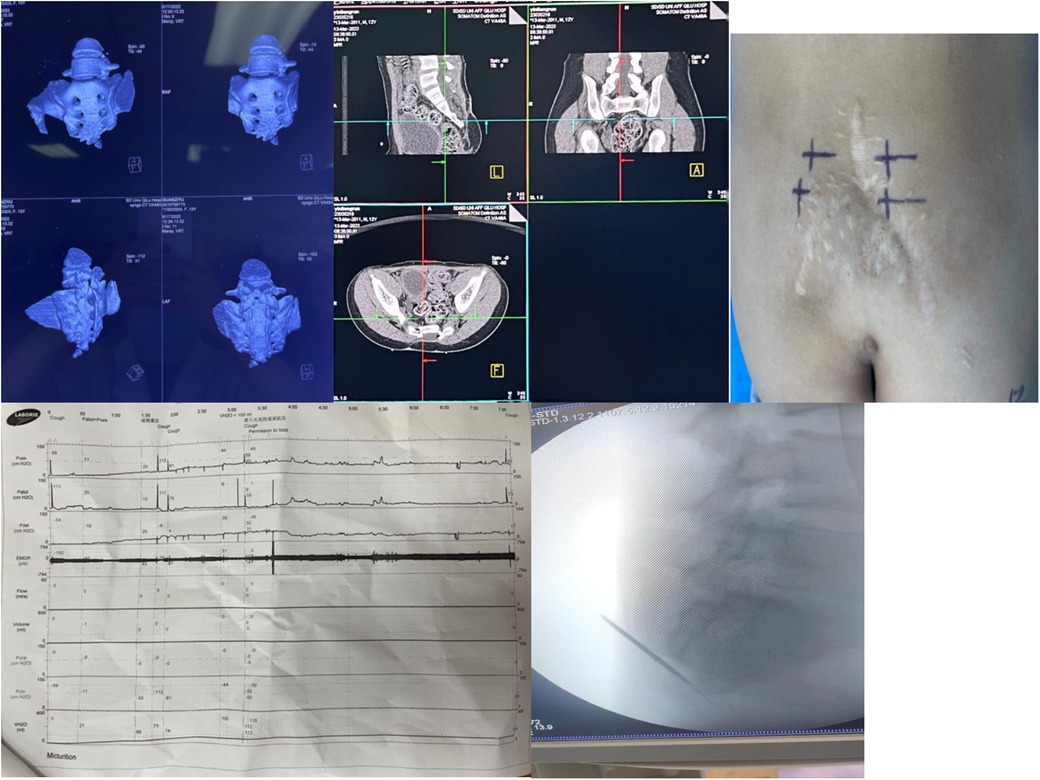

Preoperative examinations included ECG, chest x-ray, renal ultrasound, and assessment of post-void residual urine. All patients underwent 3D sacral reconstruction (Figure 1), and CT-guided localization of the S3 foramen was performed prior to surgery. In cases where sacral agenesis was identified, 3D simulated puncture localization was performed. (Due to privacy concerns expressed by patients and families, imaging data for sacral agenesis cases are not publicly disclosed.) Informed consent was obtained from all patients and their legal guardians.

Figure 1. Preoperative localization, baseline urodynamic assessment, and intraoperative electrode placement for sacral neuromodulation (SNM). (a) Preoperative sacrococcygeal three-dimensional reconstruction is performed to identify bony deformities and exclude surgical contraindications. (b) Computed tomography (CT)–based localization of the S3 foramen facilitates accurate puncture and reduces operative time. (c) The body surface puncture site is marked according to CT landmarks, and alternative puncture sites (e.g., contralateral S3, S4, or S2) are prepared in case of inadequate response at S3. (d) Baseline urodynamic testing is conducted to evaluate bladder function prior to implantation. (e) Intraoperative C-arm fluoroscopy confirms needle entry into the S3 foramen, guides puncture depth, and assists in optimal electrode positioning while ensuring procedural safety.